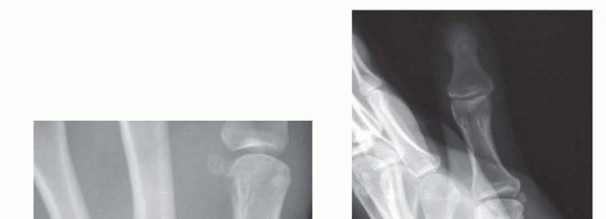

Clinical & Radiographic Imaging Archive

Definitive fixation is optimally achieved using headless compression screws. For capitate neck fractures, an antegrade trajectory (from the dorsal proximal pole directed distally into the body) or a retrograde trajectory (from the dorsal body directed proximally into the head) can be utilized, depending on fracture morphology and fragment size. The screw must be entirely buried beneath the articular cartilage to prevent devastating midcarpal impingement. Intraoperative fluoroscopy is utilized continuously to confirm anatomic reduction, verify screw length, and ensure no hardware penetrates the articular surfaces. If comminution is severe, supplemental K-wire fixation or even a miniature dorsal spanning plate may be required.

For ORIF, the fracture site is exposed by carefully elevating the hypothenar musculature originating from the hook. The fracture is reduced and provisionally held with a K-wire. A cannulated headless compression screw (typically 2.0mm or 2.4mm) is then advanced over a guidewire from the tip of the hook down into the body of the hamate. Fluoroscopy is critical to ensure the screw does not penetrate the articular surface of the hamate body or impinge upon the CMC joints.